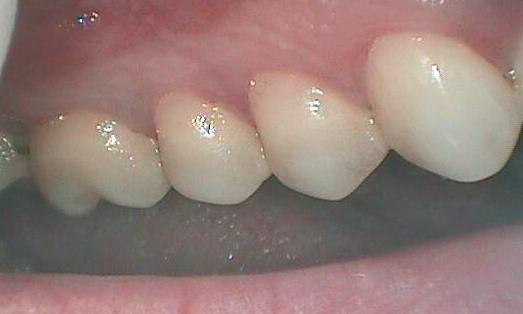

After a Pinhole gum surgery at our Glendale, CA office, your gums will be visibly farther down your teeth—reducing the appearance of receding gums and of being “long in the tooth.” Because the Pinhole Surgical Technique uses collagen strips to anchor the gum tissue instead of traditional sutures, your healing time should be shorter and less painful than if you received conventional treatment.